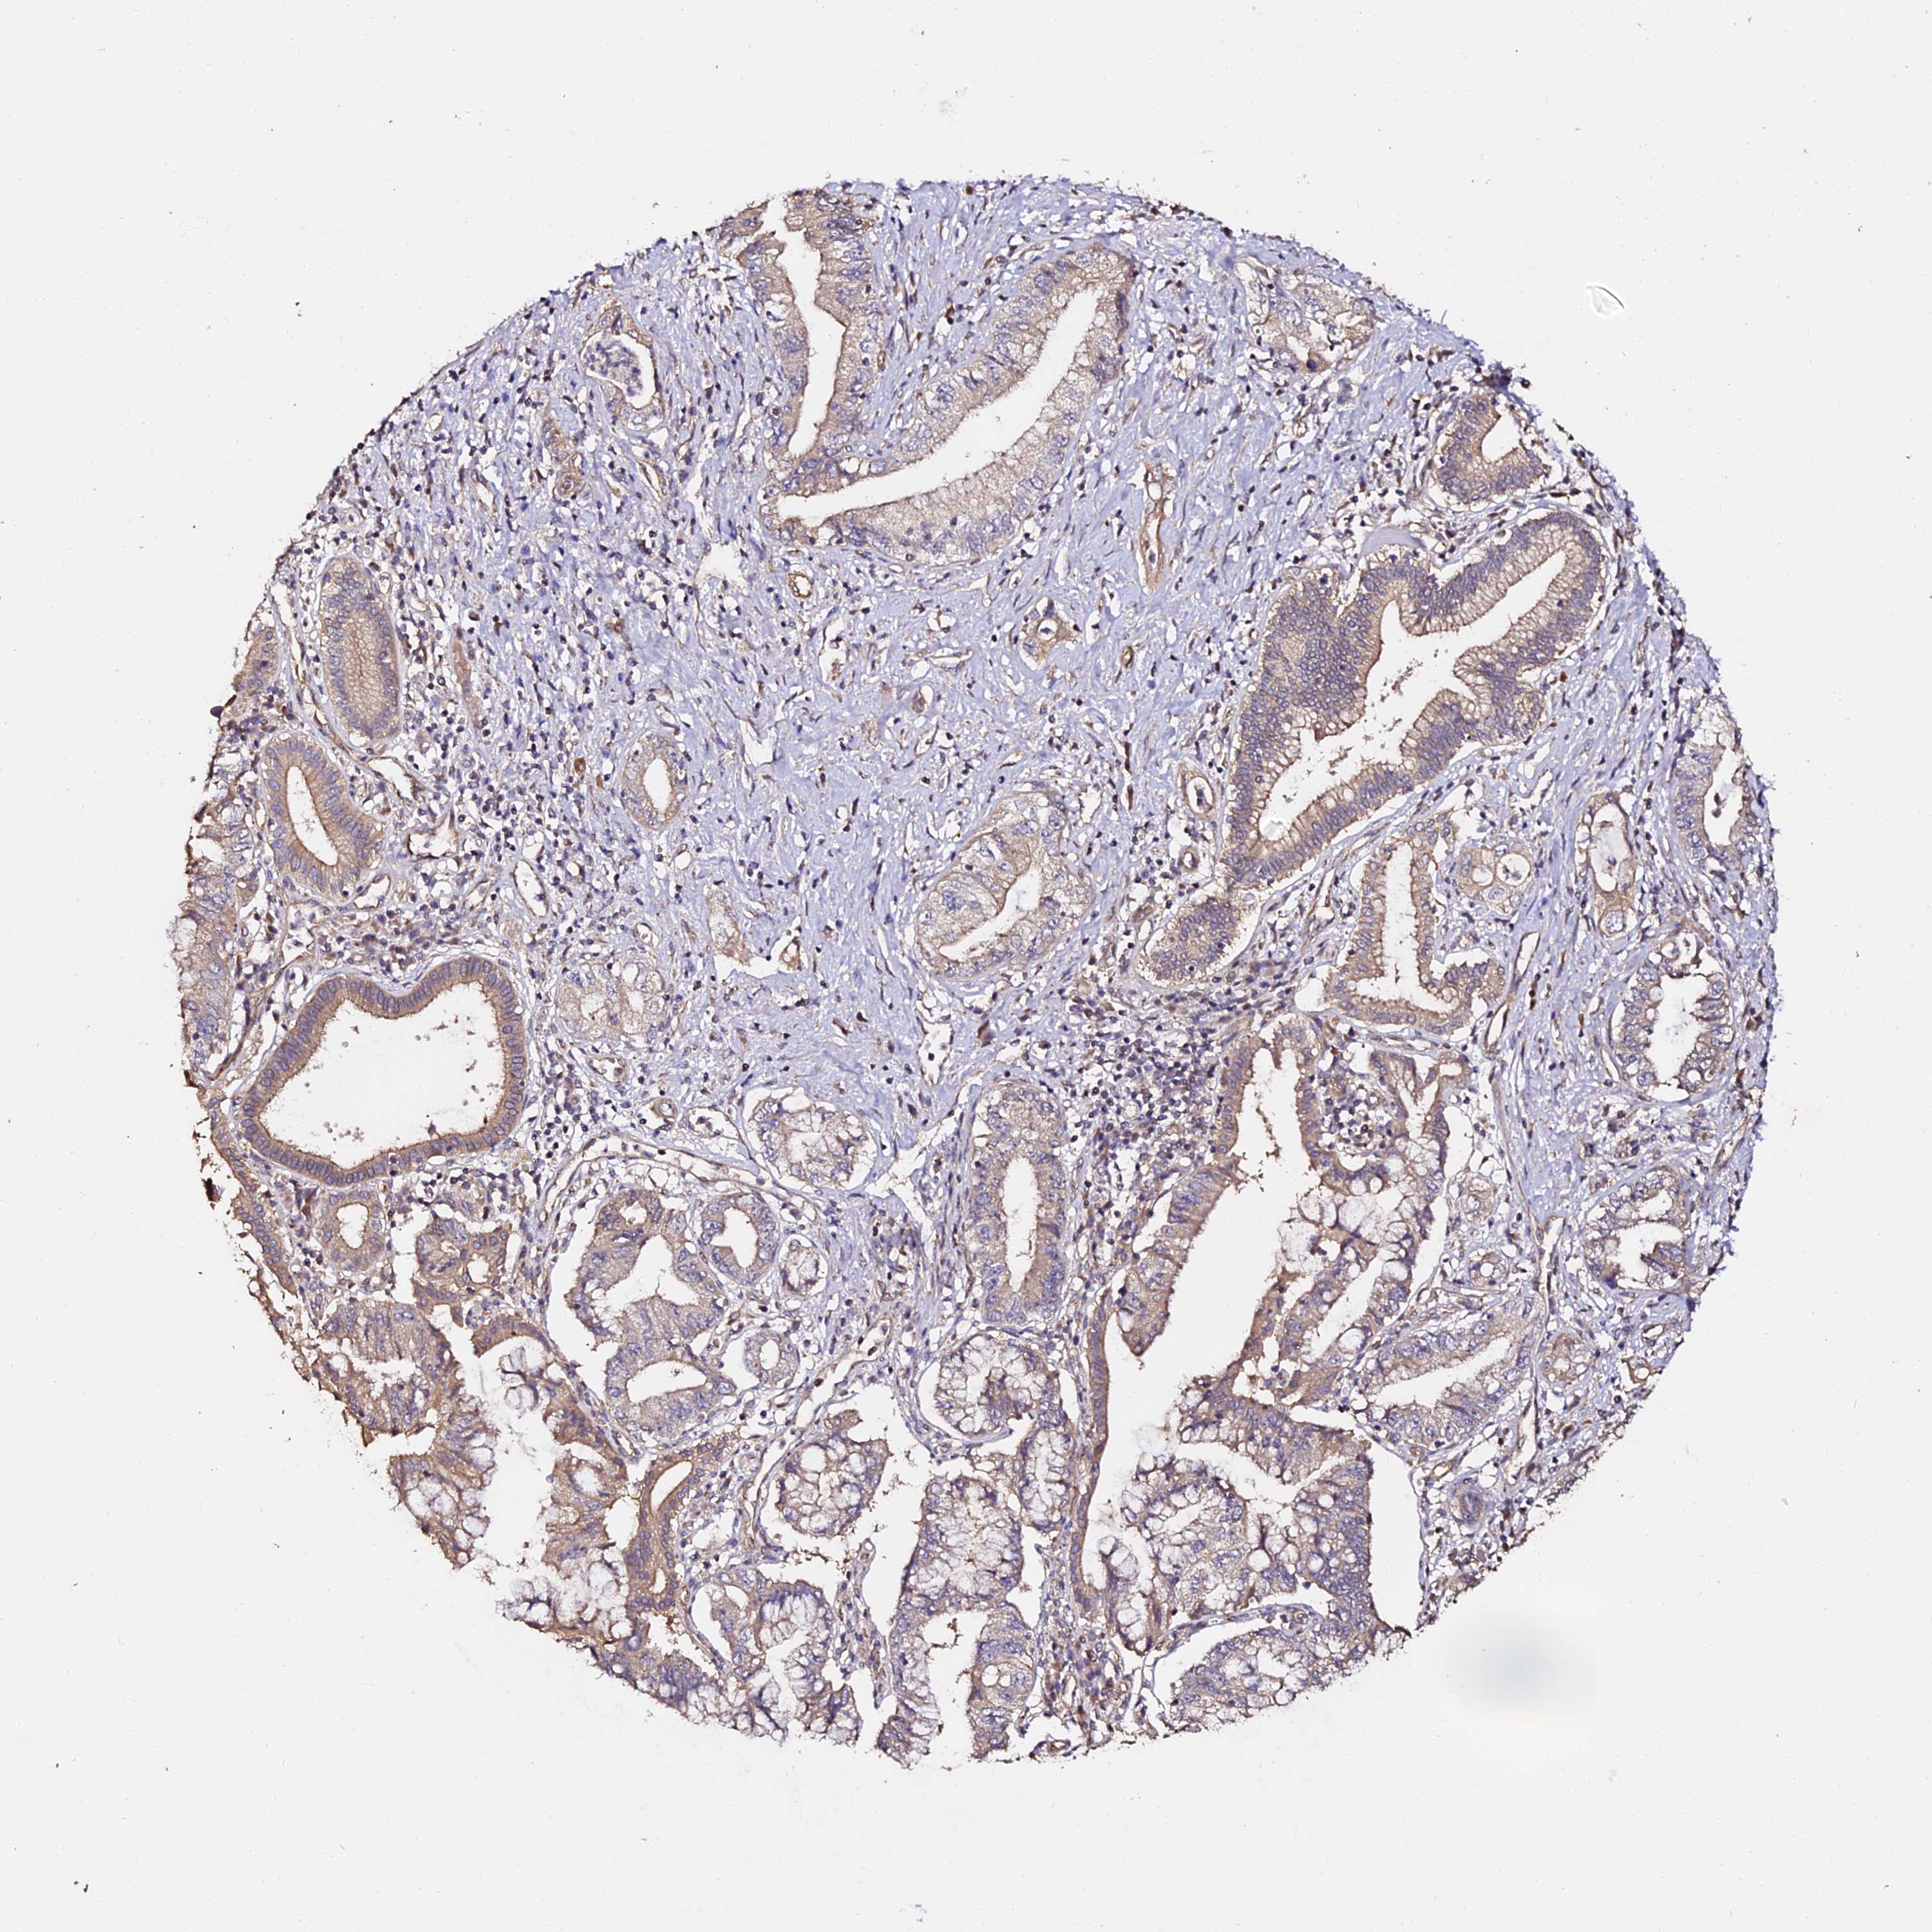

PANCREATIC CANCER - Protein expressioni

A mouse-over function shows sample information and annotation data. Click on an image to view it in a full screen mode. Samples can be filtered based on level of antibody staining by selecting one or several of the following categories: high, medium, low and not detected. The assay and annotation is described here.

Note that samples used for immunohistochemistry by the Human Protein Atlas do not correspond to samples in the TCGA dataset.

Antibody stainingi

Antibody staining in the annotated cell types in the current human tissue is reported as not detected, low, medium, or high, based on conventional immunohistochemistry profiling in selected tissues. This score is based on the combination of the staining intensity and fraction of stained cells.

Each image is clickable and will lead to virtual microscopy that enables deeper exploration of all samples and also displays staining intensity scores, fraction scores and subcellular localization as well as patient and tissue information for each sample.

Antibody HPA039611

Staining

High

Medium

Low

Not detected

Intensity

Strong

Moderate

Weak

Negative

Quantity

>75%

75%-25%

<25%

None

Location

Nuclear

Cytoplasmic/membranous

Cytoplasmic/membranous,nuclear

Adenocarcinoma, NOS